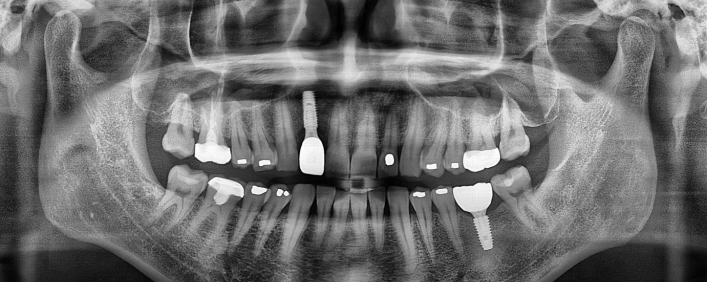

뼈이식 임플란트

치아가 상실된 채 장기간 방치되거나 잇몸 질환으로 잇몸뼈가 녹아내린 경우,

뼈의 양이 부족하여 임플란트 식립이 어려울 수 있습니다.

뼈이식 임플란트는 약하고 부족해진 잇몸뼈를 뼈이식재로 보강하여 임플란트를 식립하는 방법입니다.

임플란트 치료사례

서울스마트치과는 결과로 증명합니다.

위 치료 사례는 서울스마트치과에서 직접 치료를 받고, 환자 본인의 동의를 얻어 게재된 사진으로 무단 인용, 도용, 재배포 시 민/형사상 책임을 질 수 있습니다.